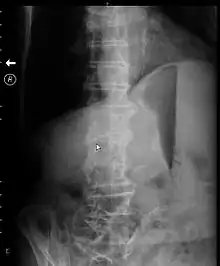

X-ray of abdomen of a person with gastric outlet obstruction taken while on their side. There is a prominent gastric air bubble, gastric air-fluid level, and a dilated stomach with particulate matter within it.

Abdominal X-ray may show a gastric fluid level which would support the diagnosis.